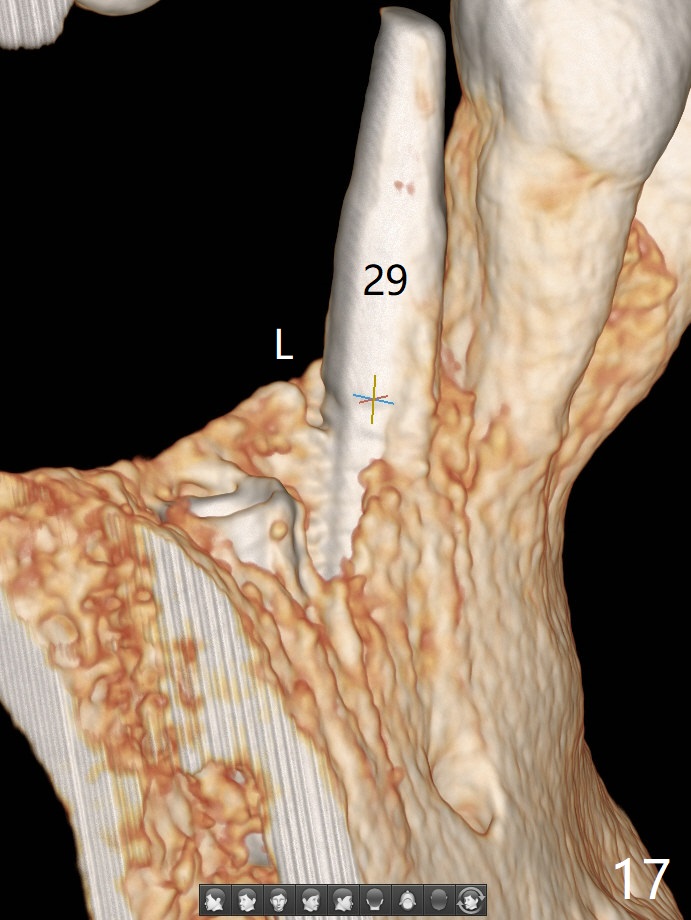

The implant at #30 was also buccally placed (Fig.6,7) and should be corrected in the same manner (Fig.7 green). Due to the bone being harder in the molar region, a smaller and shorter implant (4x11 mm vs. 5x13 mm) shifts slightly buccally while being placed (Fig.8,9). Since primary stability is lower (<20 Ncm vs. 35 Ncm associated with the implant #29), an abutment is not placed, which may be favorable to healing, but it is difficult to achieve primary closure. After bone graft (Fig.9 *) and 2 layers of PRF, Cytoplast is placed. Cytoplast appears to be exposed buccally (Fig.10 <) and occlusally (Fig.11 ^) asymptomatic 9 days postop. Exposure of Cytoplast is more distinct without sign of infection 15 days postop (Fig.12). The patient returns with chief complaint of "foul smell" 7 weeks postop (coronavirus lockdown). Although the Cytoplast exposes more (Fig.13 (* exposed; @ unexposed)), the underlying gingiva remains healthy (Fig.14). While the bone height decreases at #29, the bone density at #30 increases 4.5 months postop (Fig.15). The gingiva heals. The implant at #30 is uncovered 6 months postop. The lingual plate has to be removed for the uncover, while the coronal end of the buccal one is missing. No bone graft is added. When the 4.5x4 mm healing abutment is removed 6.5 months postop, the buccal plate looks concave at #30 (Fig.16' *). The buccal plate looks thin at #29 with a cotton roll placed buccally (Fig.16 R). The lingual plate at #29 is coronal to the buccal one (Fig.17). The buccal gingiva at #29 is quite long (Fig.18). The coronal buccal plate appears to be missing (Fig.19 >), which will be watched. A 4.5x7.5(4) mm cemented abutment is torqued (Fig.20).